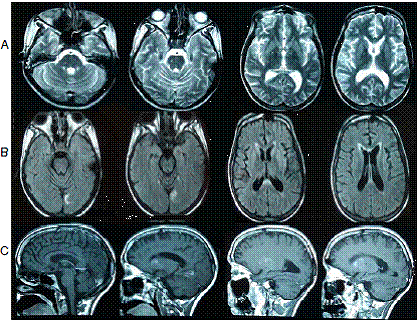

Pasado el primer mes tras el alta, la paciente fue evaluada medicamente para iniciar el proceso de rehabilitación neurológica y se reportó que permanecía postrada en cama, su interacción con el medio era limitada, seguía sin movimiento voluntario en las extremidades, abría los ojos de forma espontánea y no podía hablar. Se le hizo una resonancia magnética cerebral que sugirió la presencia de daño axonal difuso, pero el hallazgo no fue concluyente dado que fue necesario utilizar secuencias rápidas por las condiciones de la paciente (figura 1).

Con el apoyo de la familia, de los terapeutas y de los médicos, se inició desde ese momento estimulación sensorial, sensoperceptiva y motora durante dos meses en casa, con lo cual se logró dar comienzo a un proceso de rehabilitación intensivo (cinco horas diarias de lunes a viernes, durante un mes) en un centro de rehabilitación de Medellín, donde se utilizaron técnicas de neurorrehabilitación motora y sensorial a cargo de un equipo interdisciplinario de terapeutas y médicos. Con ellas, la paciente logró recuperar la marcha entre el tercer y el cuarto mes después del egreso hospitalario.